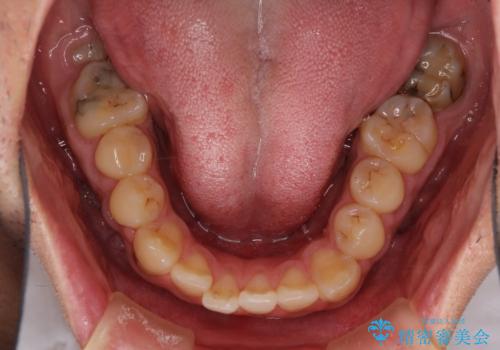

- 前歯のデコボコと上下のクロスバイトを気にして来院された患者様です。

インビザラインを用い、IPR(歯と歯の間を削る)と歯列全体を拡大させることで、歯並びを整えていくこととしました。

上の前歯が下の前歯を乗り越える際、奥歯がほとんど咬めない時期があり、乗り越えた後も、インビザライン特有の奥歯の咬みにくさが続きました。

咬み合わせ改善のために治療期間を要しましたが、最終的に奥歯はしっかりと咬めるようになりました